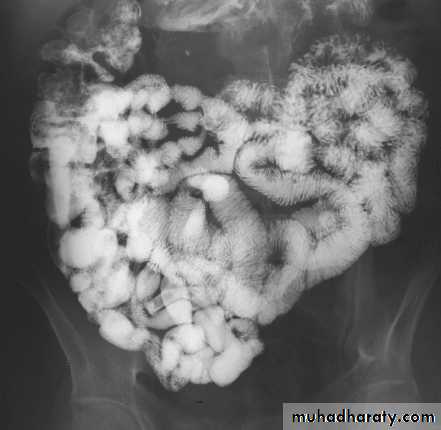

Crohn's disease

It is non-specific granulomatous inflammatory disease of unknown etiology, it nearly always affect the terminal ileum or other several parts of the small and large intestine, leaving normal intervening bowel, forming the skip lesions.The major radiological signs on barium examinations are :

1.strictures(string sign) are variable in length2.contraction of the cecum, this is seen with a diseased terminal ileum

3.dilatation of the bowel may be seen proximal to narrowed areas

4.ulcers :are quite deep. Fine ulceration + mucosal edema=cobblestone appearance

5.thickening,distortion and effacement of mucosal folds

6.separation of loops of bowel due to bowel wall thickening or an inflammatory mass

7.fistula to other loops of SB, colon, bladder or vagina

8.signs of malabsorption